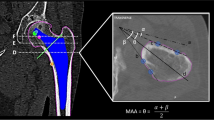

To eliminate the need for locator pin implantation and its potential pin-related complications (e.g., postoperative pain at the site of pin implantation [9]), a proprietary non-pin-based surface registration technique was developed by the manufacturer in 2000. First, a CT scan of the femur is performed according to the manufacturer’s specified protocol. The CT data are then imported into the workstation, and surface models of the proximal and distal femur are created for surface registration (Fig. 11.7). A preoperative plan is created in the same manner as with the pin-based registration system (Fig. 11.3). Once the surface bone model is successfully created and the optimal surgical plan completed, the surgeon transfers the data to a CD.

Prior to the surgical procedure, the surgeon loads the CD’s information into the robotic system and performs routine setup and diagnostic checks. During surgery, the surgeon secures the patient’s leg in the femoral fixator of the robot and then locates the bone surface points on the femur using a digitizer (Think Surgical) (Fig. 11.8a). In the present study, 14 points from the proximal femur and three points from the distal femur were digitized (Fig. 11.8b). The robotic computer recorded the spatial information of surface points and matched them to the coordinate surface model that was created preoperatively on the workstation. This procedure is called surface registration. When the registration has been completed, the surgeon verifies its accuracy by touching bone surfaces with the digitizer. If the difference between the digitization-based surface contour and the CT-derived surface contour is within 1 mm, the registration is considered acceptable (Fig. 11.8c). A drill bit is then installed, and the milling of the femur begins.

Pinless registration technique. (a) During the operation, the surgeon oriented the robot by selecting points on the femoral surface using a “digitizer.” (b) Registration of the proximal femur. Fourteen points were chosen, as shown on the monitor. The surgeon verified the registration accuracy by touching the bone surfaces with the digitizer. (c) If the locations coincided with the bone surface points on the monitor, the surgeon accepted the registration